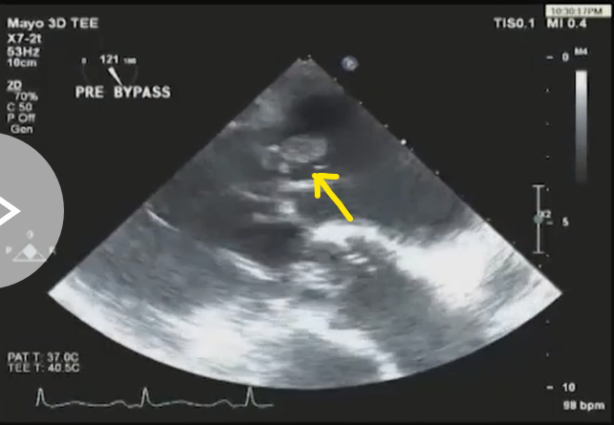

此培训为MAYO诊所推出的心内科fellow系列培训之一,主要目的是能够使大家学习到AMI以后心脏机械并发症的识别和诊断,还有ACS的非心脏的并发症的表现,以及临床中存在与ACS临床上有相似之处的非心脏疾病。 急性心肌梗死后出现的并发症,分为心脏性和非心脏性的,心脏并发症又包括心电学方面的并发症以及机械并发症,非心脏性并发症包括血栓栓塞和出血,还可能出现与心包相关的并发症。 心脏机械并发症包括就是破裂性和非破裂性的2类,破裂性并发症包括游离壁破裂、室间隔穿孔和乳头肌断裂,其中游离壁破裂既可能是直接的穿孔,也可以是亚急性破裂形成假性动脉瘤这样包容性的破裂。而非破裂性机械并发症包括严重的左室心力衰竭,右室梗塞,左室壁动脉瘤以及缺血性二尖瓣反流。 从根本上来说,这些严重并发症的发生都与心脏的泵功能衰竭有关,泵功能的衰竭造成了血流动力学不稳定以及基线的电不稳定性。 第一节:非破裂性机械并发症 非破裂性机械并发症,即严重的左室心力衰竭——心源性休克,右室梗塞,左室壁动脉瘤以及缺血性二尖瓣反流。 1、 心源性休克:在心梗发生时,发生心源性休克的主要原因就是大面积的心肌梗死,那么如果要导致心脏泵功能衰竭,左室心肌质量至少要损失40%以上。其他导致心源性休克的原因还有右室梗塞、心脏破裂以及快速和缓慢性心律失常。 2、 右室梗塞:也是导致心源性休克发生的重要原因。在下壁心梗的患者中,大概有33%的患者同时也发生右室梗死,这种情况多见于RCA近端闭塞,与高死亡风险相关。在所有下壁STEMI者中都要考虑是否同时存在RV梗塞,心电图V1和RV4导联ST段抬高超过1mm为其特异性心电图改变(图1)。 图1. 右室梗塞的心电图表现 3、 右室梗塞为什么会导致患者发生心源性休克呢?从病理生理上讲,右室急性缺血时会致其收缩不良,导致RV每搏输出量和峰压降低,继而是左室前负荷降低,心输出量降低;另一方面,急性缺血还同时使右室舒张功能受损,此时右心充盈压显著增加,并且由于右室急剧扩张,会在心包内占据很大体积,使得心包内压力显著增加,这些综合造成的结果使RV和LV的充盈减少。左心充盈压下降而右心压力不断升高,最终导致低血压、肺血流减少、颈静脉压升高,其临床结果可能类似于心包填塞以及缩窄性心包炎。 4、 左室壁动脉瘤(图2):首先提出一个问题供大家思考,以下有关左室壁动脉瘤的说法哪一个是正确的?1左室壁动脉瘤只局限于心内膜下;2有一个相对狭窄的颈部;3是否都与前壁心梗有关;以及4容易有血栓的附着,并且心包是组成瘤壁的一部分。实际上,左室壁动脉瘤在STEMI后的发生率<5%,前壁梗死的患者更易发生,及时进行再灌注治疗可以降低其发生率。它突出于心腔外侧,瘤壁就是左室壁,颈部和底部的比例大约是1:1,可以出现附壁血栓。所以上述说法中只有3是正确的。 图2. 左室壁动脉瘤示意图,O;颈部,D:底部,LA:左心房,LV:左心室,AO:主动脉 5、 缺血性二尖瓣反流:为心梗后左室重构所致,表现为乳头肌移位、乳头肌功能不良使瓣叶活动受限以及瓣环扩张(图3)。治疗的焦点集中于及时的再灌注治疗、利尿剂的应用和后负荷的降低,如果遗留严重的二尖瓣反流,则会导致心梗后的远期生存率下降。 图3. 瓣环扩张(A)、乳头肌功能不良致瓣叶活动受限(B)导致大量MR 第二节:破裂性机械并发症 破裂性并发症包括游离壁破裂、室间隔穿孔和乳头肌断裂,其中游离壁破裂既可能是直接的穿孔,也可以是亚急性破裂形成假性动脉瘤这样的包容性破裂。大多数破裂性并发症都发生在AMI的第一个24小时之内,剩余的则发生在1周之内。通过超声心动图可以发现MI的机械并发症,包括急性乳头肌断裂、下段室间隔断裂、上段室间隔断裂以及二尖瓣脱垂。 1、 乳头肌断裂所致二尖瓣反流(图4):乳头肌断裂常发生在MI后的2~7天,急性缺血事件发生时,从心外到心内的压力梯度增加,心内灌注降低,乳头肌属于心内结构,缺血的敏感性增加。一旦出现需要外科手术治疗。 图4. 乳头肌断裂(箭头所示) 2、 室间隔缺损(图5):属于MI后的罕见并发症,多于梗死后3~5天发生,在梗死后即刻或者第一个24小时内就可以发生,部分与患者进行的纤溶治疗有关。由于再灌注治疗的开展,目前发生率已经由2%降至0.2%。破裂发生在健康心肌和坏死心肌的交界处,在前壁心梗时,缺损位于室间隔心尖部,下壁心梗时缺损则位于下-后间隔基底段,RV梗死及功能失常者预后不良。 图5. 前壁心梗(A)、下壁心梗(B)所致不同部位室间隔穿孔 3、 游离壁破裂:急剧的、常为致死性机械并发症;发生率<1%;MI后死亡约8~24%是由此而造成;通常在梗死后的5天内发生。好发因素包括1首次心梗,2前壁心梗,3老年患者以及4女性。 4、 亚急性破裂:是一种特殊类型的游离壁破裂,占所有游离壁破裂患者的约1/3,是因为附壁血栓和心包覆盖了穿孔部位所致,局部表现为假性动脉瘤(图6),临床上常比较隐匿,并且可能仅通过UCG发现,因此任何超声发现的心脏周围局部积液都需要引起怀疑并详细扫查。与真性动脉瘤(即左室壁动脉瘤)不同,假性动脉瘤的颈部狭窄,颈部与底部的比值<0.5,心包是瘤壁的组成部分。亚急性破裂的进展常是难以预测,可以进展至完全破裂乃至心包填塞,因此需要外科治疗。 图6. 左室假性动脉瘤示意图,O;颈部,D:底部,LA:左心房,LV:左心室,AO:主动脉 第三节:AMI的非心脏并发症 AMI的非心脏并发症主要包括血栓栓塞和出血,以及心包并发症。那么下面关于左室血栓的说法哪个是正确的呢?1下壁心梗更为常见,2如果不予治疗栓塞风险可达50%,3栓塞的风险取决于血栓的移动性和是否凸出于腔内。左室血栓常(图7)见于大面积前壁心梗,在再灌注前时代其发生率可高达40%,有再灌注治疗后这一几率已降至4~15%;经胸超声心动图是发现LV血栓的第一选择;心脏MRI的敏感性更高,但与超声心动图的特异性相似。由于心梗后不运动和运动障碍的室壁区域存在静止血流,因此如容易在局部形成附壁血栓。如果梗死部位为心尖部,且左室EF值减低达<30%,则存在血栓栓塞的高风险。如果未治疗,左室血栓发生栓塞的风险为10~15%,这一风险的高低还取决于栓子的移动性和是否突出于心腔内,早期且持续的抗凝治疗(3~4个月)可以降低栓塞风险。 图7. 左室心尖部附壁血栓 一图总结心脏机械并发症 第四节:类似ACS的非心脏疾病 通过一个有趣的病例,我们来学习一下在临床中可能存在类似于ACS表现的非心脏疾病。这是一个77岁老年女性,症状为头晕、恶心、呕吐,急诊CT除外了急性卒中,但心肌坏死标记物升高,心电图提示为Af、并且下壁前壁导联T波倒置,但超声心动图上仅表现为室间隔中下段至左室心尖部运动减低,没有看到下壁及前壁的运动异常。随后患者出现严重的高血压和心动过缓,并存在定向力、消化不良和眼球震颤,继续监测头CT及MRI,结果发现枕叶大面积脑梗。实际上,早在1947年,急性卒中所引起的ECG变化就已经被报道,病程中出现深大的倒置T波则被称为神经源性T波。在急性颅内事件发生时可以存在肌钙蛋白的升高以及心电图出现ST-T改变,在卒中的急性期,ECG诊断急性心梗的特异性会降低。 除急性脑血管病以外,以下疾病也会出现类似于ACS的临床发现,包括心电图异常和心肌坏死标记物升高,如特发性应激性心肌病,主动脉夹层,肺栓塞等等,需要及时进行诊断及鉴别诊断。 最后需要强调的是,超声心动图是发现AMI后心脏机械并发症的最重要检查,AMI发生后一周内必须行UCG检查以发现隐匿的高危并发症。